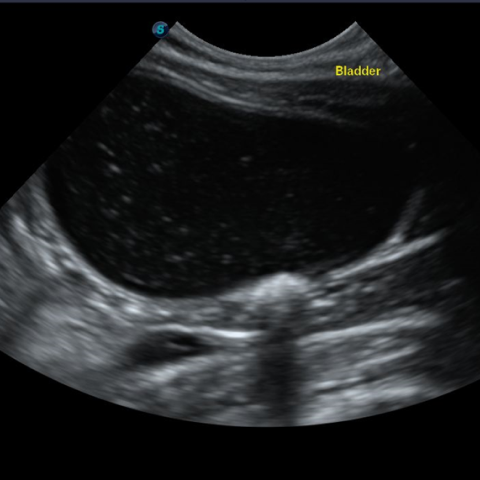

±âº»ÀûÀ¸·Î ¿µ»ó °Ë»ç(¹æ»ç¼± °Ë»ç, ÃÊÀ½ÆÄ °Ë»ç)¿Í ¿ä°Ë»ç·Î ¹æ±¤ÀÇ Æó»ö ¿©ºÎ, ¿°Áõ, °á¼®, ¼¼±Õ °¨¿° ¿©ºÎ¸¦ ÆÇ´ÜÇϰí, ³ë·ÉÀ̰ųª Áõ»óÀÌ ½ÉÇÒ °æ¿ì ½ÅÀå ¼öÄ¡¿Í ÀüÇØÁú ¼öÄ¡ µîÀ» üũÇϱâ À§ÇÑ Ç÷¾×°Ë»ç°¡ ÇÊ¿äÇÒ ¼ö ÀÖ½À´Ï´Ù.

¸¸¾à °í¾çÀ̰¡ 24½Ã°£ ÀÌ»ó ¼Òº¯ÀÌ ¾ø°í, º¹ºÎ¸¦ ¸¸Á®º¸¾ÒÀ» ¶§ ¹æ±¤ÀÌ ÆØÃ¢µÇ¾î ÀÖ´Â °ÍÀÌ ´À²¸Áö¸é ¿äµµ Æó»ö »óÅÂÀÏ °¡´É¼ºÀÌ ³ôÀ¸¹Ç·Î ÃÖ´ëÇÑ ºü¸¥ ½Ã°£ ³»·Î º´¿øÀ» ¹æ¹®ÇÏ¿©¾ß ÇÕ´Ï´Ù. Ç÷´¢¶ó°í ÇØµµ ¼Ò·® ¾¿ÀÌ¶óµµ ¼Òº¯À» º¸°í ÀÖ´Ù¸é ÀÀ±Þ »óȲÀº ¾Æ´Õ´Ï´Ù. ÇÏÁö¸¸ Ç÷´¢´Â ºñ´¢±â°èÀÇ ½É°¢ÇÑ ¹®Á¦°¡ ÀÖÀ½À» ÀǹÌÇϹǷΠº´¿ø¿¡¼ Á¤È®ÇÑ »óŸ¦ È®ÀÎÇØ¾ß ÇÕ´Ï´Ù.

¹æ±¤¿°ÀÇ °æ¿ì ȯ¹¦ÀÇ »óŰ¡ ¾ÈÁ¤ÀûÀ̶ó¸é ¾à¹°À» ó¹æ ¹ÞÀº µÚ Åë¿ø Ä¡·á°¡ °¡´ÉÇÕ´Ï´Ù. ÇÏÁö¸¸ ¿äµµ Æó»öÀ¸·Î ÀÎÇØ ¿äµµ Ä«Å×Å͸¦ ÀåÂøÇØ¾ß Çϰųª ½ÅÀå ¼öÄ¡°¡ ¿À¸¥ ½ÅºÎÀü »óÅÂ, ¶Ç´Â °á¼®À» Á¦°ÅÇϱâ À§ÇØ ¼ö¼ú µî ¿Ü°úÀûÀΠóġ°¡ ÇÊ¿äÇÏ´Ù¸é ÀÔ¿ø Ä¡·á¸¦ ÇØ¾ß ÇÕ´Ï´Ù.